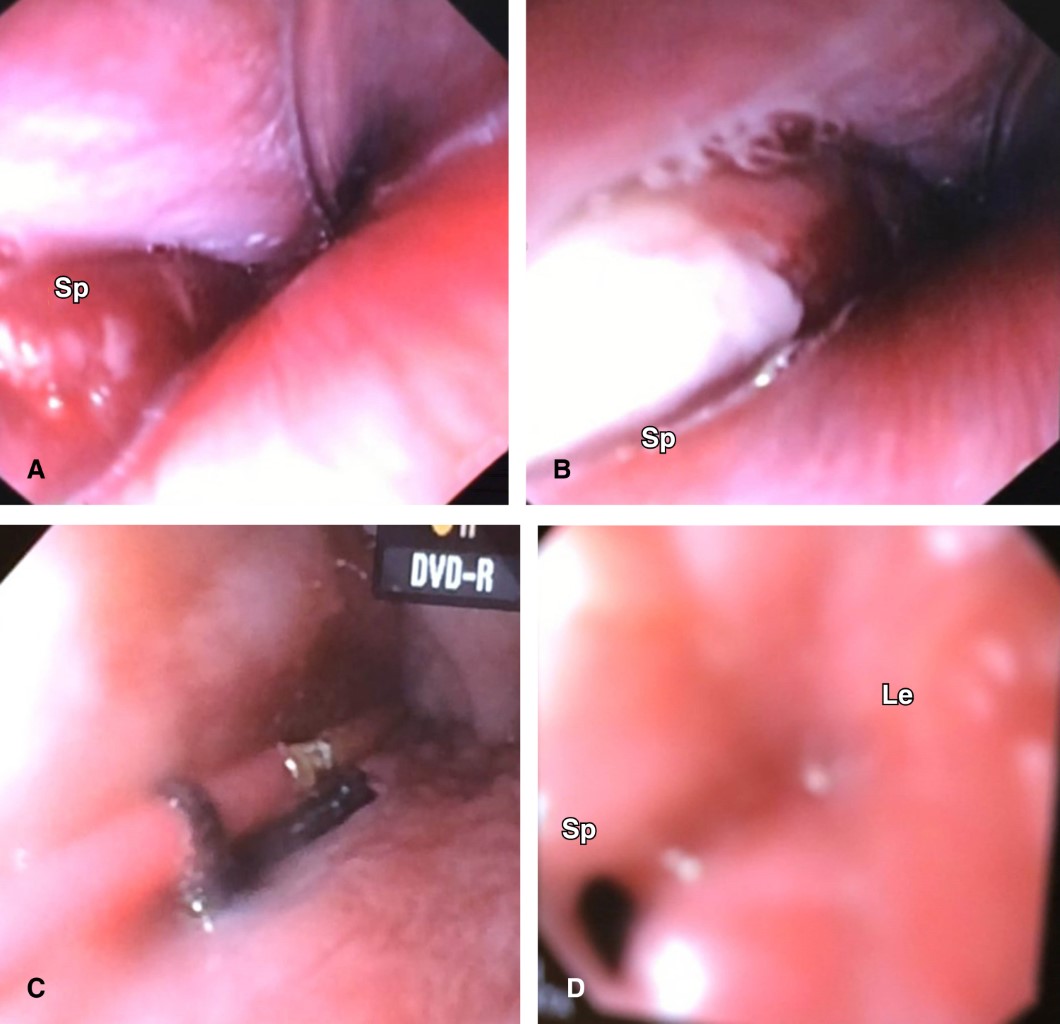

Para precisar el sitio de la potencial perforación esofágica se realizó un estudio endoscópico digestivo superior que se documenta en región lateral izquierda e inmediatamente superior a esfínter cricofaríngeo en hipofaringe, sitio de perforación con emisión de exudado purulento por donde se avanza a través del canal de trabajo 20 cm de una sonda de aspiración tipo Fogarty de 3 French obteniéndose 50 mL de pus y residuos necróticos (Figura 3).

Con dos semanas de irrigación y drenaje se eliminó el gasto purulento, se retiró la sonda dual dirigida a mediastino y se corroboró la involución del absceso en la tomografía. Al persistir el trayecto fistuloso faringocutáneo con gasto de saliva como una verdadera esofagostomía cervical (en el tracto del drenaje de Penrose simple) se realizó nueva endoscopia digestiva superior con paso a estómago sin estenosis residuales y con la presencia de un doble trayecto fistuloso: uno faringocutáneo comunicado al exterior largo y otro faringomediastinal comunicado al interior del mediastino corto de 2 cm. La cavidad mediastinal con tendencia hacia la obliteración por tejido de granulación permitió instilar por vía endoscópica a través del canal de trabajo con un catéter de 3 French una solución de cianoacrilato 10 mL como adhesivo tisular en el interior de todo el doble trayecto fistuloso, disminuyendo notablemente el gasto de saliva por la fístula faringocutánea hasta su cierre completo una semana después. En la evolución posterior no hubo disfagia, tolerando la vía oral, y control con serie esofagogastroduodenal sin secuelas ni complicaciones (Figura 5).